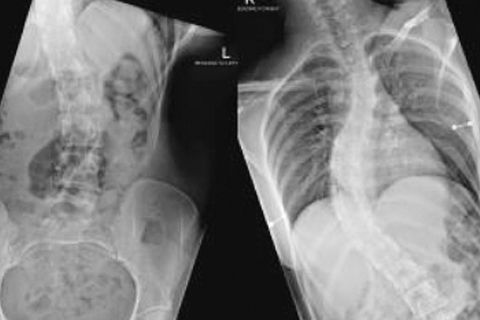

Conferma Sì, sono un operatore sanitario. Cancella No, non sono un operatore sanitario.Caso clinico di Ennovate® in scoliosi idiopatica complessa di un adolescente, eseguito da Bronek Boszczyk e Oded Hershkovich nel Centro medico della Queen, Nottingham, Regno Unito. Il caso è stato presentato durante il Nspine Meeting 2018 in Svizzera e pubblicato anche in Spinal News International a giugno 2018.